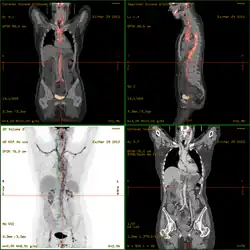

La vasculitis engloba todos aquellos síndromes y enfermedades que cursan con inflamación de los vasos sanguíneos (vénulas, capilares y arteriolas de mediano y gran calibre) tanto de órganos específicos como generalizadas.[1][2]